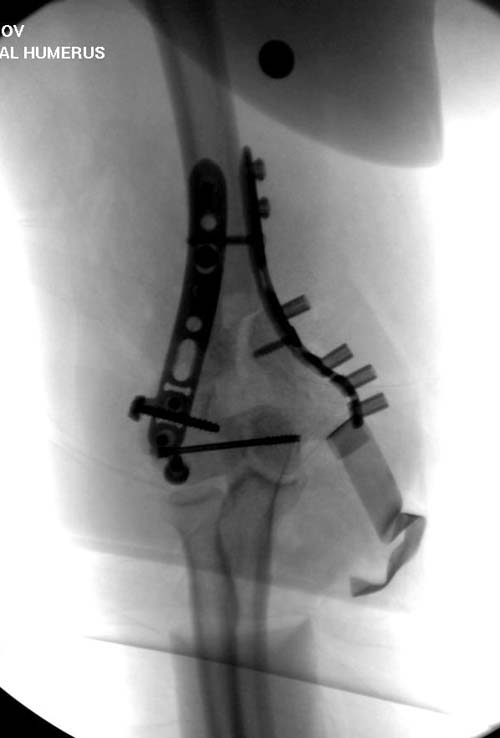

Здесь открытый перелом, временный наружный фиксатор и окончательная фиксация пластинами. Второй случай фиксация без остеотомии отростка пластинами Biomet-DePuy...